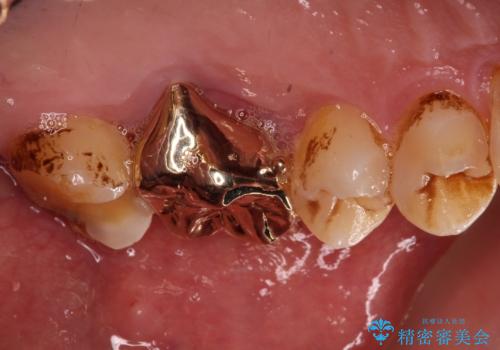

根管治療後に、歯根にまで及んでしまった破折部分を適切な位置に変更するため、歯槽骨の削除を伴う外科処置を行い、その後補綴治療を行うこととしました。

強い咬合力により歯が破折したため、補綴物は歯へのダメージの最も少ないゴールドクラウンを選択しました。